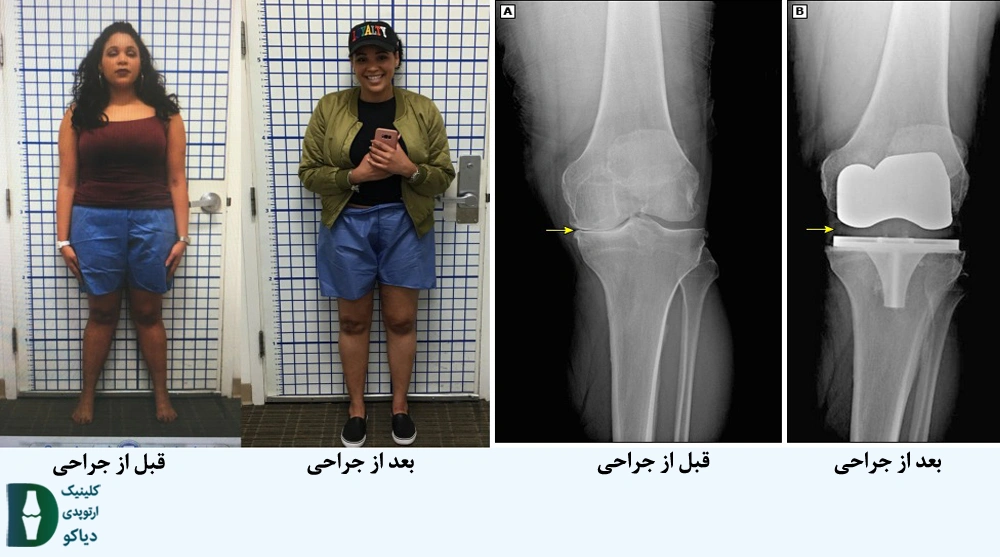

در شکل زیر نمونه ای از قبل و بعد از جراحی تعویض مفصل زانو دیده میشود: